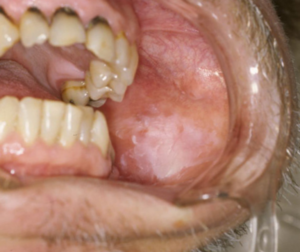

白板症

白板症は、歯ぐきや舌、頬の粘膜にできる白色の板状または斑点状の角化性病変で、口腔がんへ進行するリスクが高いとされる病変です。

触れた際に痛みを感じたり、食べ物がしみたりすることもありますが、痛みを伴わないケースも多く、歯科検診で初めて発見されることもあります。

特徴としては、白い板状の範囲が徐々に広がり、硬く盛り上がっていて擦っても取れない点が挙げられます。

発症には、義歯の不適合や歯の金属の詰め物による粘膜刺激、ビタミンA・Bの不足、喫煙習慣などが関連しているといわれています。